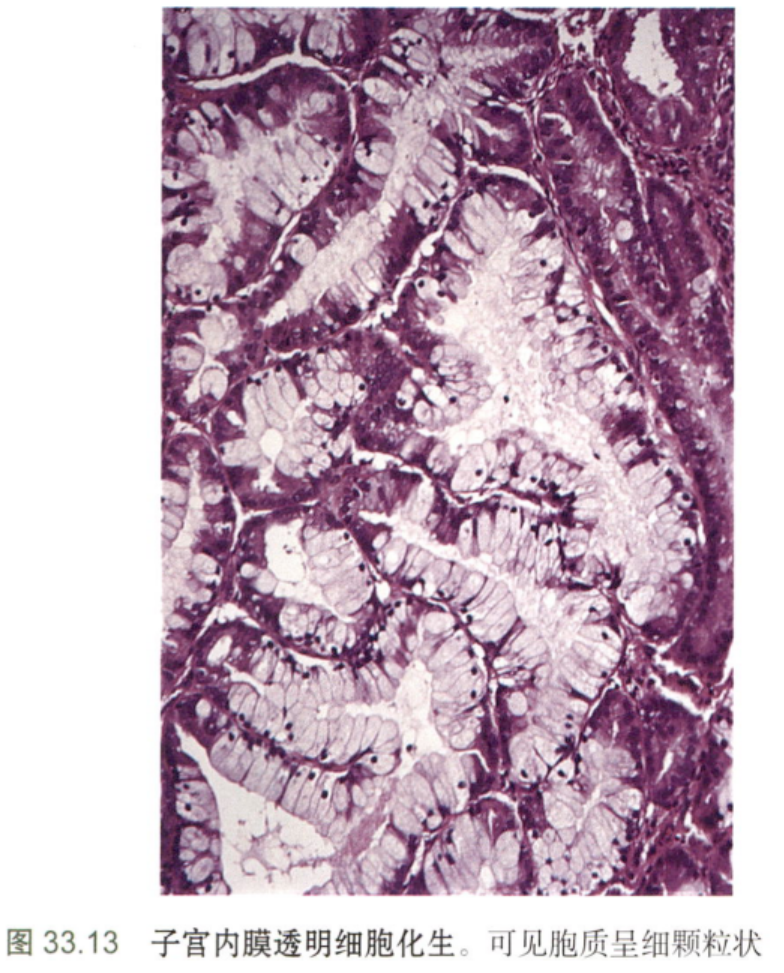

·鞋钉状和透明细胞化生

上皮细胞呈高柱状,胞质透明,细胞核位于顶端。需要与透明细胞(中肾管)腺癌进行鉴别